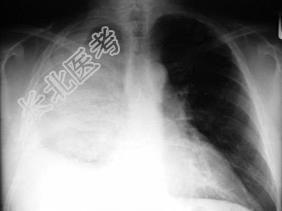

- 单项选择题男,59岁, 呼吸困难,胸痛, 有发热,请结合CT图像选择最可能的诊断 ( )

A、脓胸

B、肺脓肿

C、大叶性肺炎

D、肺囊虫病

E、肺癌